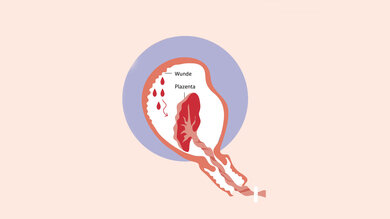

Wochenfluss

Für den Körper ist der Wochenfluss enorm wichtig. Löst sich nach der Geburt des Babys die Plazenta von der Gebärmutter, entsteht eine Wunde. Ihre Heilung geht mit Blutungen und Ausfluss einher, der Schleimhaut und Gewebereste aus dem Körper schwemmt. Er dauert vier bis sechs Wochen an. Mit der Zeit verändern sich Menge, Farbe und Konsistenz.

Zunächst ist der Wochenfluss blutig, im Verlauf wird er bräunlich oder gelblich, gegen Ende eher weiß. Anfangs sind die Blutungen meist deutlich stärker, als Frauen es von ihrer Periode kennen. Nach einem Kaiserschnitt ist der Wochenfluss insgesamt meist weniger stark. Hygiene ist wichtig, damit sich die Wunde in der Gebärmutter nicht infiziert: etwa die Vorlagen alle zwei bis vier Stunden wechseln, danach die Hände waschen. Anders als früher angenommen, enthält der Wochenfluss keine Krankheitserreger. Versiegt er plötzlich, ist das ein Alarmzeichen.